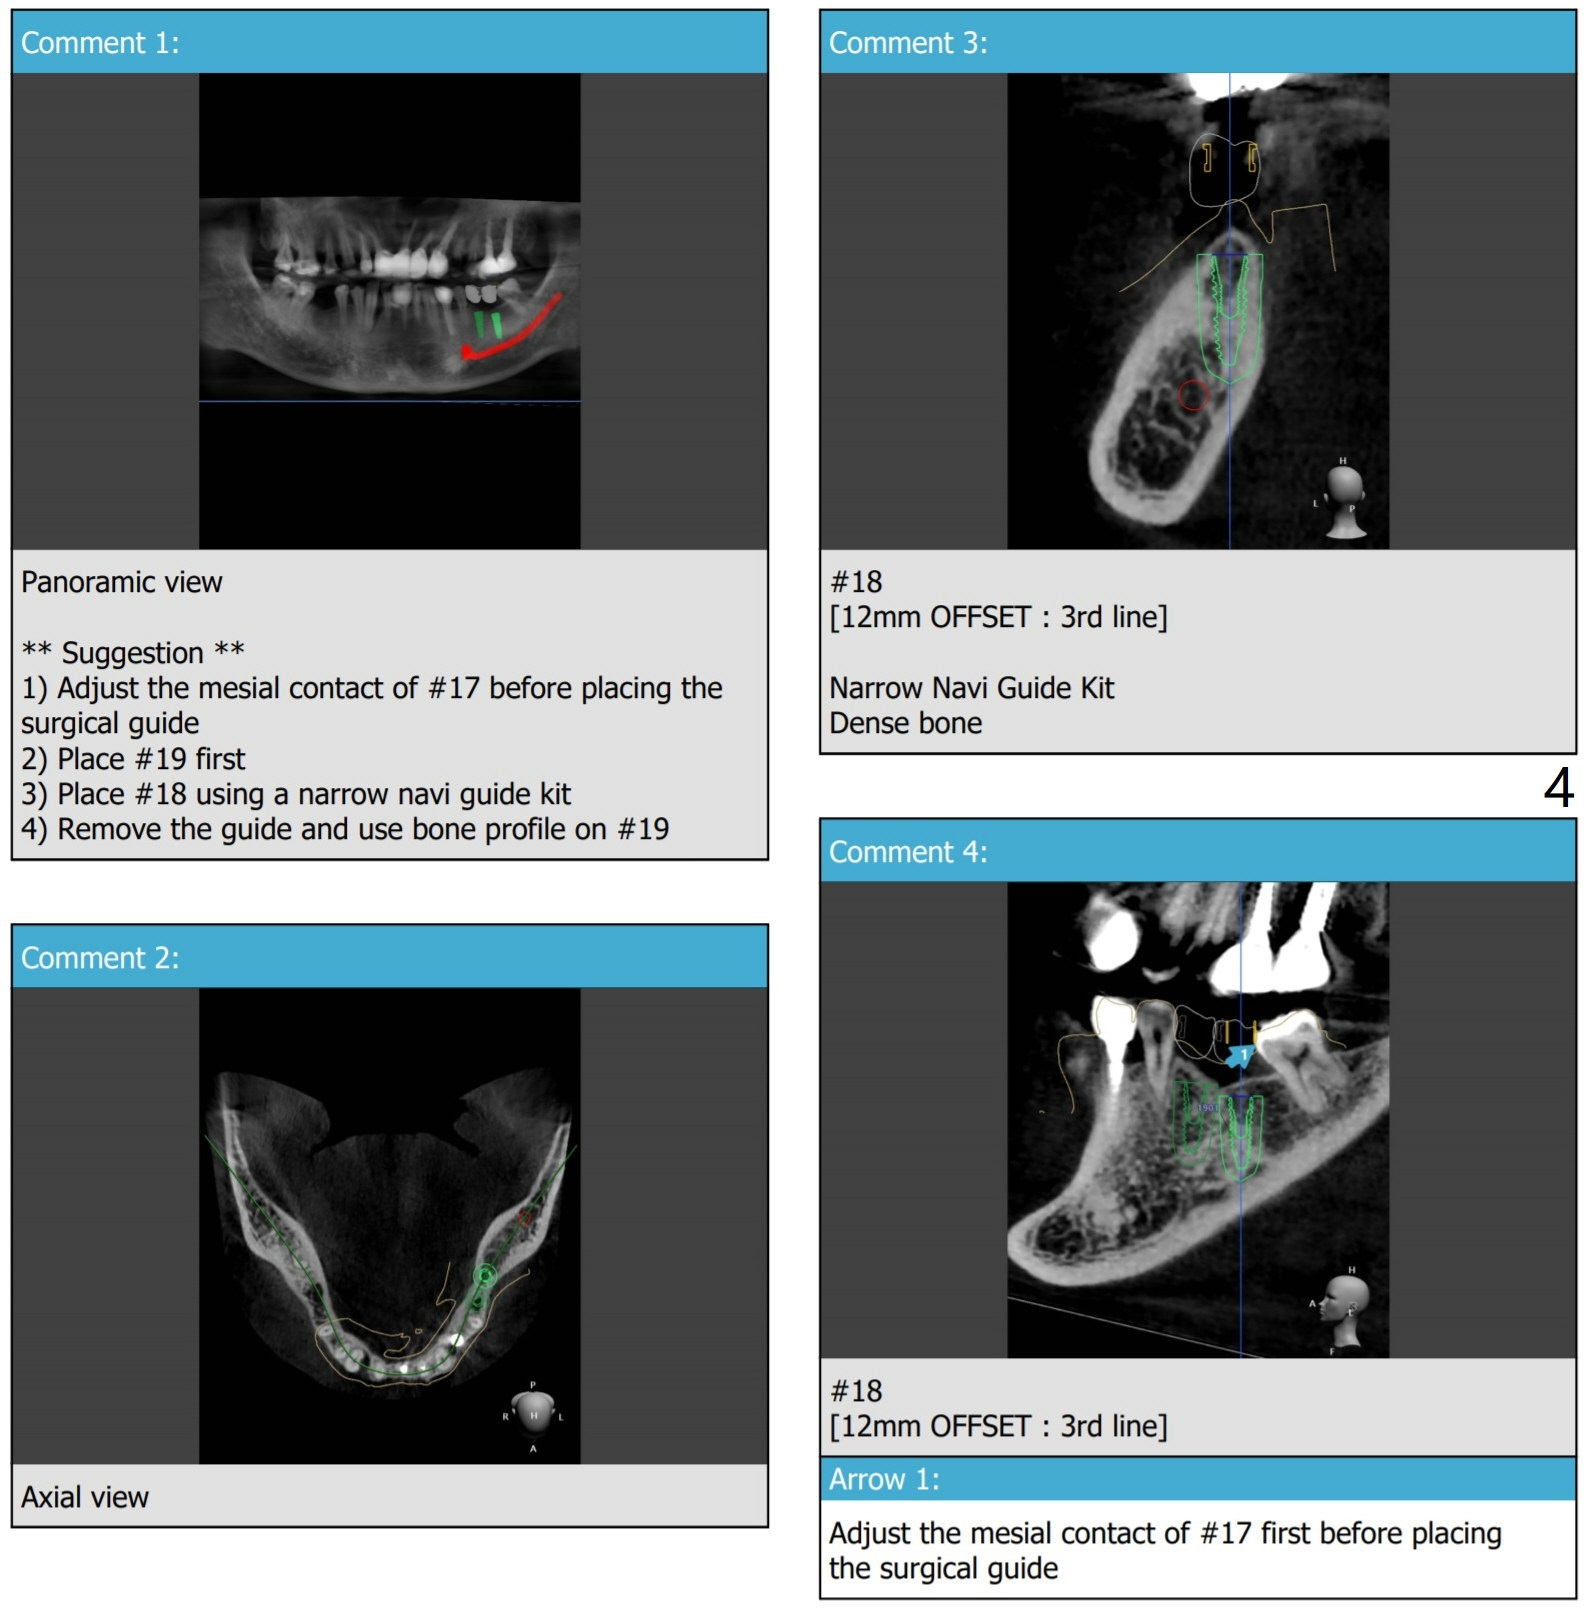

Trim #17 mesial before seating guide